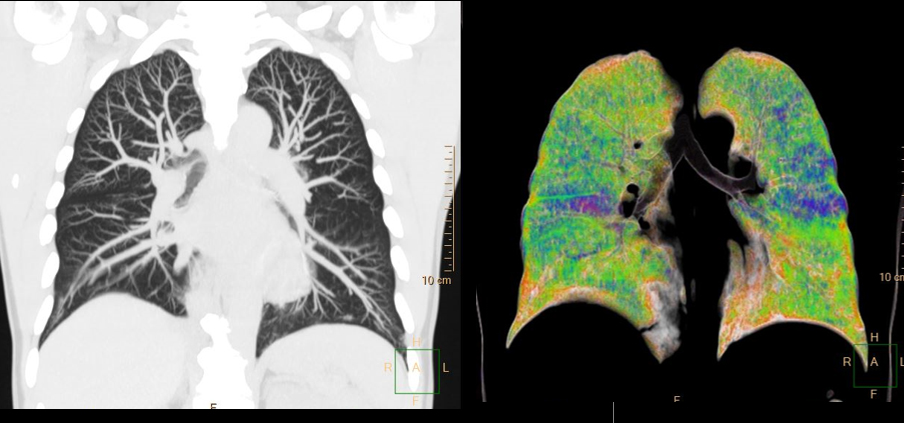

- Precise Suite with AI for the Philips Incisive CT. The solution combines advances in AI reconstruction techniques and camera-based workflow, for motion-free cardiac scans and interventional procedures. Philips Incisive enhances the CT experience for patients and staff while controlling costs across the organization to help meet the most pressing financial, clinical and operational goals.

- Incisive can accommodate a wide range of patients and exam types with high image quality.